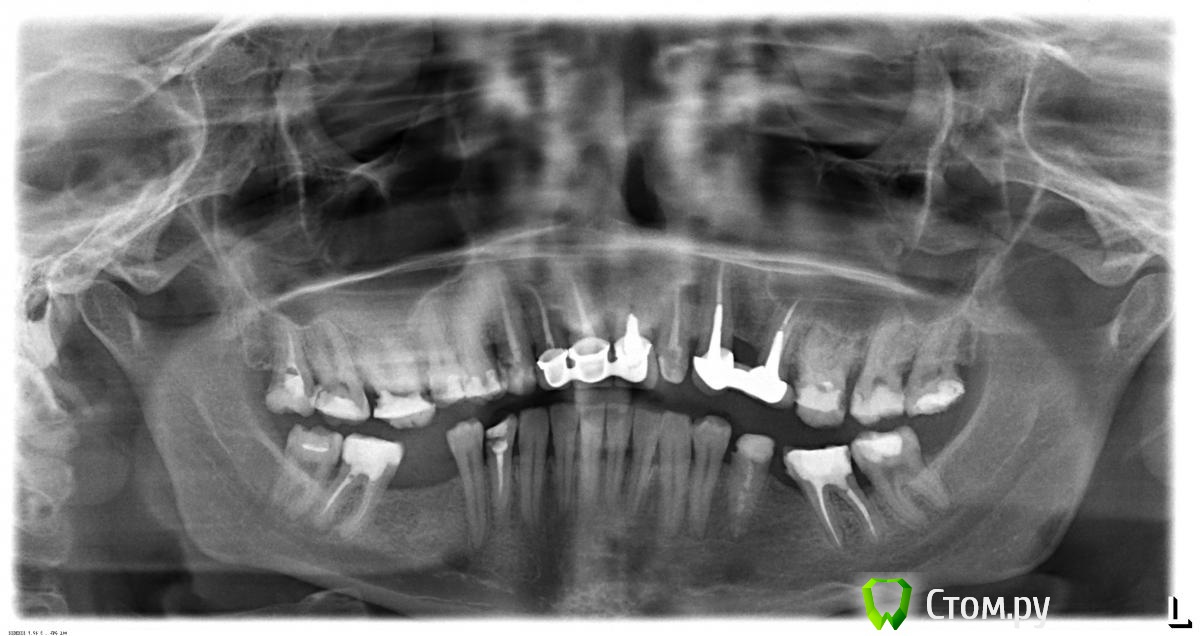

Татьяна М. Опубликовано 23 октября, 2014 Поделиться Опубликовано 23 октября, 2014 , Возможно ли поставить имплант (на снимке слева), И верхний зуб смещается вниз, возможно ли его закрытие коронкой, обязательно ли его надо будет депульпировать? Спасибо. Ссылка на комментарий

anvladd Опубликовано 23 октября, 2014 Поделиться Опубликовано 23 октября, 2014 ну скорее справа,а вот 16 зуб пролечить каналы и сделать культевую вкладку и коронку. Ссылка на комментарий